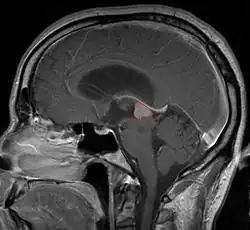

Пинеалома — опухоль головного мозга, исходящая из шишковидного тела. Это гетерогенная группа новообразований, локализующихся в пинеальной области (задние отделы III желудочка, область цистерны четверохолмия) и имеющих различное происхождение. Развитие пинеаломы может быть связано с опухолевой трансформацией пинеалоцитов, астроцитов или гоноцитов[2][3]. Опухоль, развившаяся из пинеалоцитов, в зависимости от степени дифференцировки носит название пинеоцитома, пинеальная паренхиматозная опухоль промежуточной дифференцировки, пинеобластома. Опухоли астроцитарного происхождения имеют типичное строение. Наиболее характерным для астроцитомы является медленный, инфильтративный рост.

Симптомы опухоли обусловлены её расположением. Наиболее частыми симптомами являются головные боли, тошнота и рвота. Они обусловлены повышением внутричерепного давления вызванного обструктивной гидроцефалией, которая возникает при сдавлении опухолевой массой водопровода мозга и нарушением циркуляции спинномозговой жидкости.

Компрессия верхнего двухолмия опухолью приводит к синдрому Парино - невозможности вертикальных движений глаз, небольшой дилатации зрачка. Возможно развитие отёка соска зрительного нерва